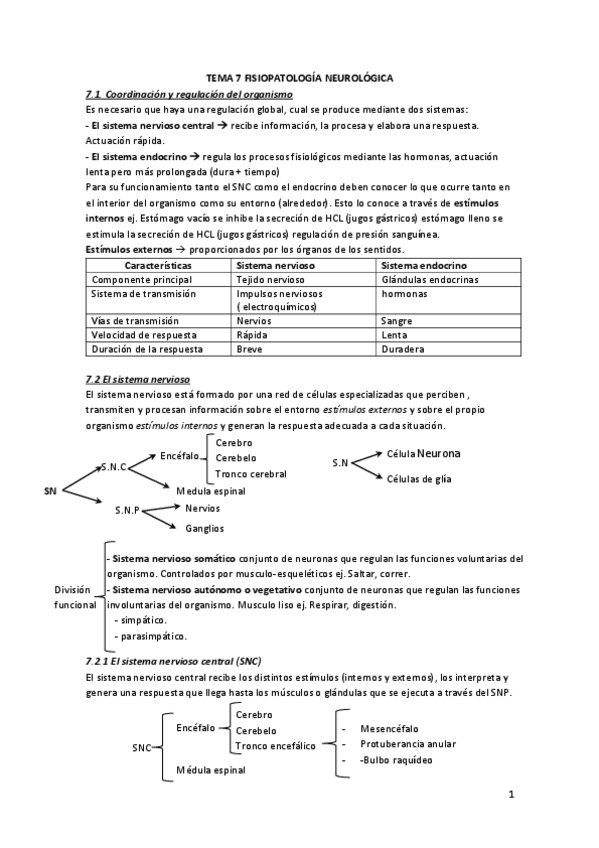

He publicado nuevos apuntes de Fisiopatología general: Tema-7-Fsiopatologia-neurologica.pdf